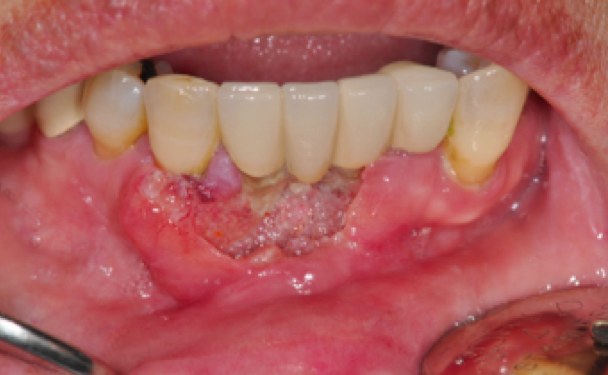

설암![]() |

치은암![]() |

구개암(입천정)![]() |

구강저암(혀아래)![]() |